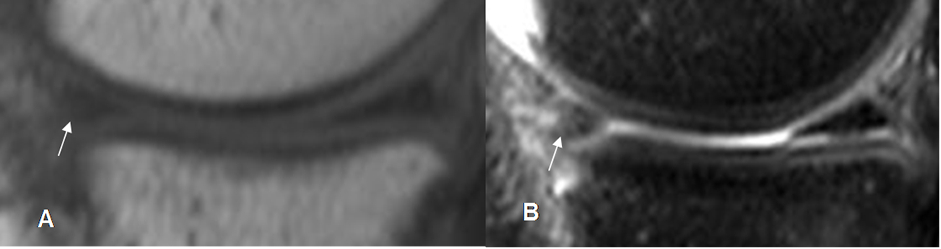

Fig 71. Ruptura meniscal horizontal.

A: RM sagital en T1 y B: RM sagital en STIR. Imagen en sentido horizontal que se comunica el borde libre y la superficie articular inferior, por ruptura meniscal.